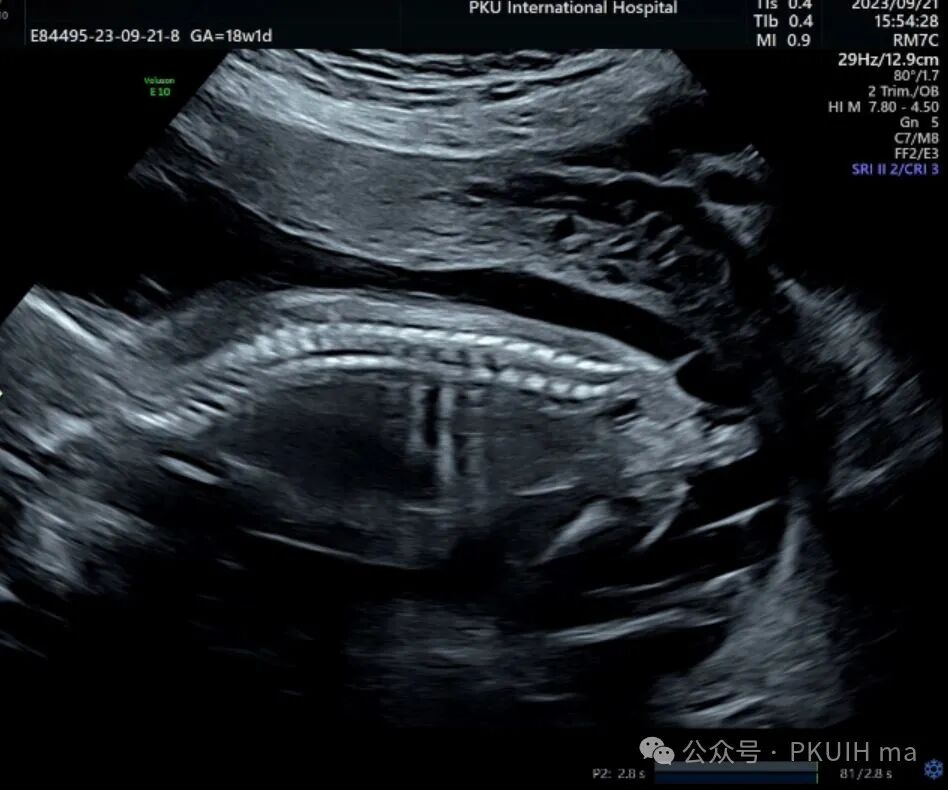

上图是18周发现的骶尾部畸胎瘤